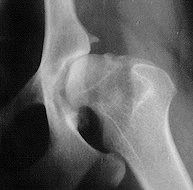

Die Röntgenbefunde teilt man nach dem Grad der veränderung ein !

HDO(A) frei .

HD1(B) (Verdacht)

HD2(C) leichte HD.

HD3(D) mittlere HD.

HD4 (E) schwere HD.

gesunde Hüfte Hund mit HD